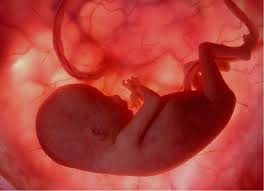

Anne Karnındaki Bebek Nelerden Etkilenir?

anne karnındaki bebek nasıl etkilenir,anne karnındaki bebeğin ruhsal gelişimi,anne karnındaki bebek nelerden etkilenir,anne karnındaki bebeğin gelişim süreci hakkında bilgiler

Hamilelikte ruh halinizin, yediklerinizin, dinlediğiniz müziğin bebeğin gelişimini etkilediğini biliyor musunuz?

Annenin hamileyken beslenmesi ile bebeğin karakteri arasında ilişki var mı? Anne karnındaki bebekle anne arasında duygusal bir bağ olu mu? Anne karnında bebek hangi sesleri duyar? Hamilelik sürecinde yaşr bebeğin karakterini etkiler mi?

Bebek, rahim içinde gelişmeye başladığı andan itibaren sinir hücreleri oluşmaya, özellikle hamileliğin 8. haftasından itibaren beyin içindeki hücreleri birbirleriyle iletişim kurmaya başlar. Bu da bebek daha 8 haftalıkken hafıza oluşmaya başlıyor demektir. Daha da büyüdükçe, hafızadan sonra anne babadan aldığı özelliklere bağlı olarak bebeğin kişiliğine ait ilk özellikleri oluşmaya başlar.

Beyin gelişimi hamileliğin 32’nci haftasına kadar çok hızlı devam eder, 32’nci haftadan sonra, çocuk 5 yaşına gelene kadar hızla gelişmeye devam eder. Beyinle ruhsal gelişim arasında paralellik vardır. Beyin hücreleri arasındaki iletişimi ne kadar iyi sağlarsanız, çocuk daha zeki olsun, hafızası güçlensin diye yaptırılan alıştırmalara benzerlerini rahim içinde yaparsanız büyük yarar sağlarsınız.